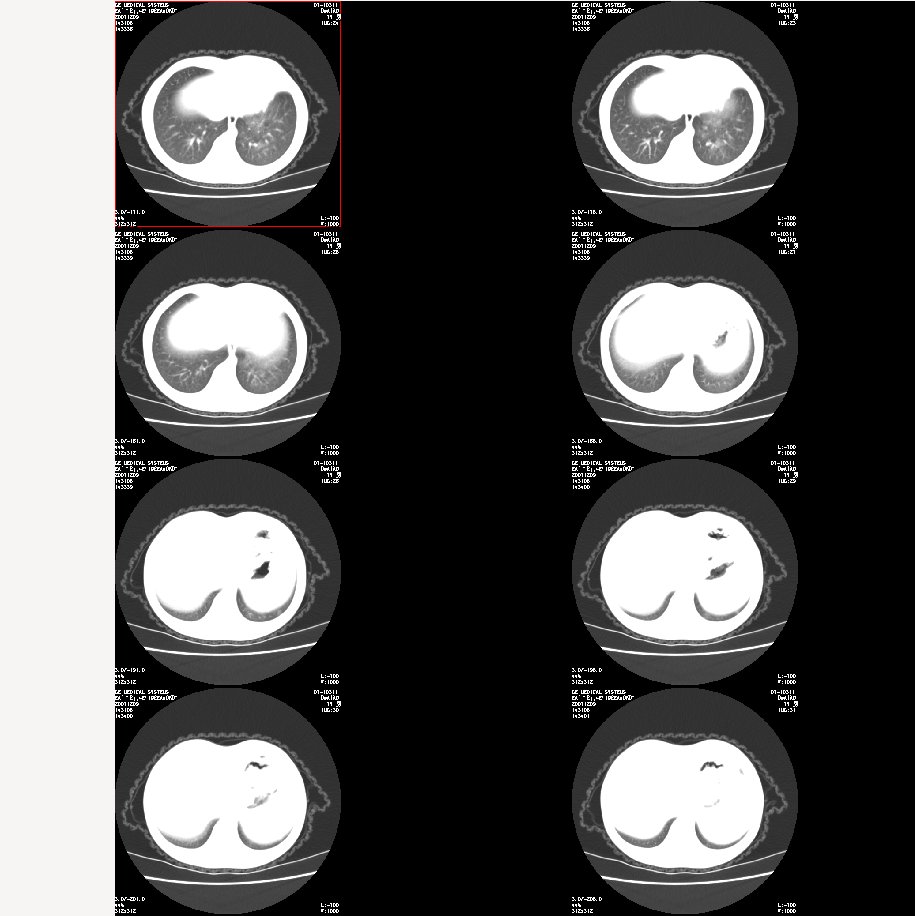

m 7

咳嗽、咯血半月。查体:双肺呼吸音粗,可及干湿鸣。自诉每年均有发作。

肺窗: